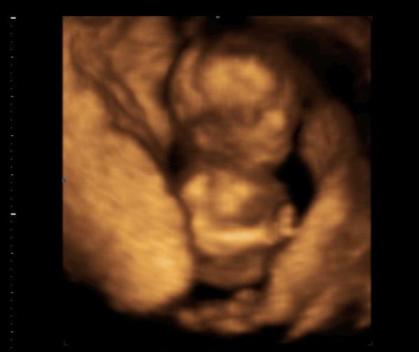

ma voltunk 4D-n, de nem írtam. :lol: Csak kicseréltem a fotót :lol:

Kép

Nagyon édi a babóca! :D Hogyhogy nem írtál róla??? :shock:

Akkor esetleg már azt is tudjátok, hogy kislány lesz-e vagy kisfiú? :wink:

az új képen első látásra nekem úgy tűnik, mintha egy védelmező kézben lenne a babátok :) tetszik! a neme nem derült ki esetleg? :wink:

Kata, olyan helyes a Pindur-Pandur!! :)

Kata gyönyörű a kis babócád, a kép is nagyon jól sikerült. Hol csinálták?A nemét nem tippeltékmeg?